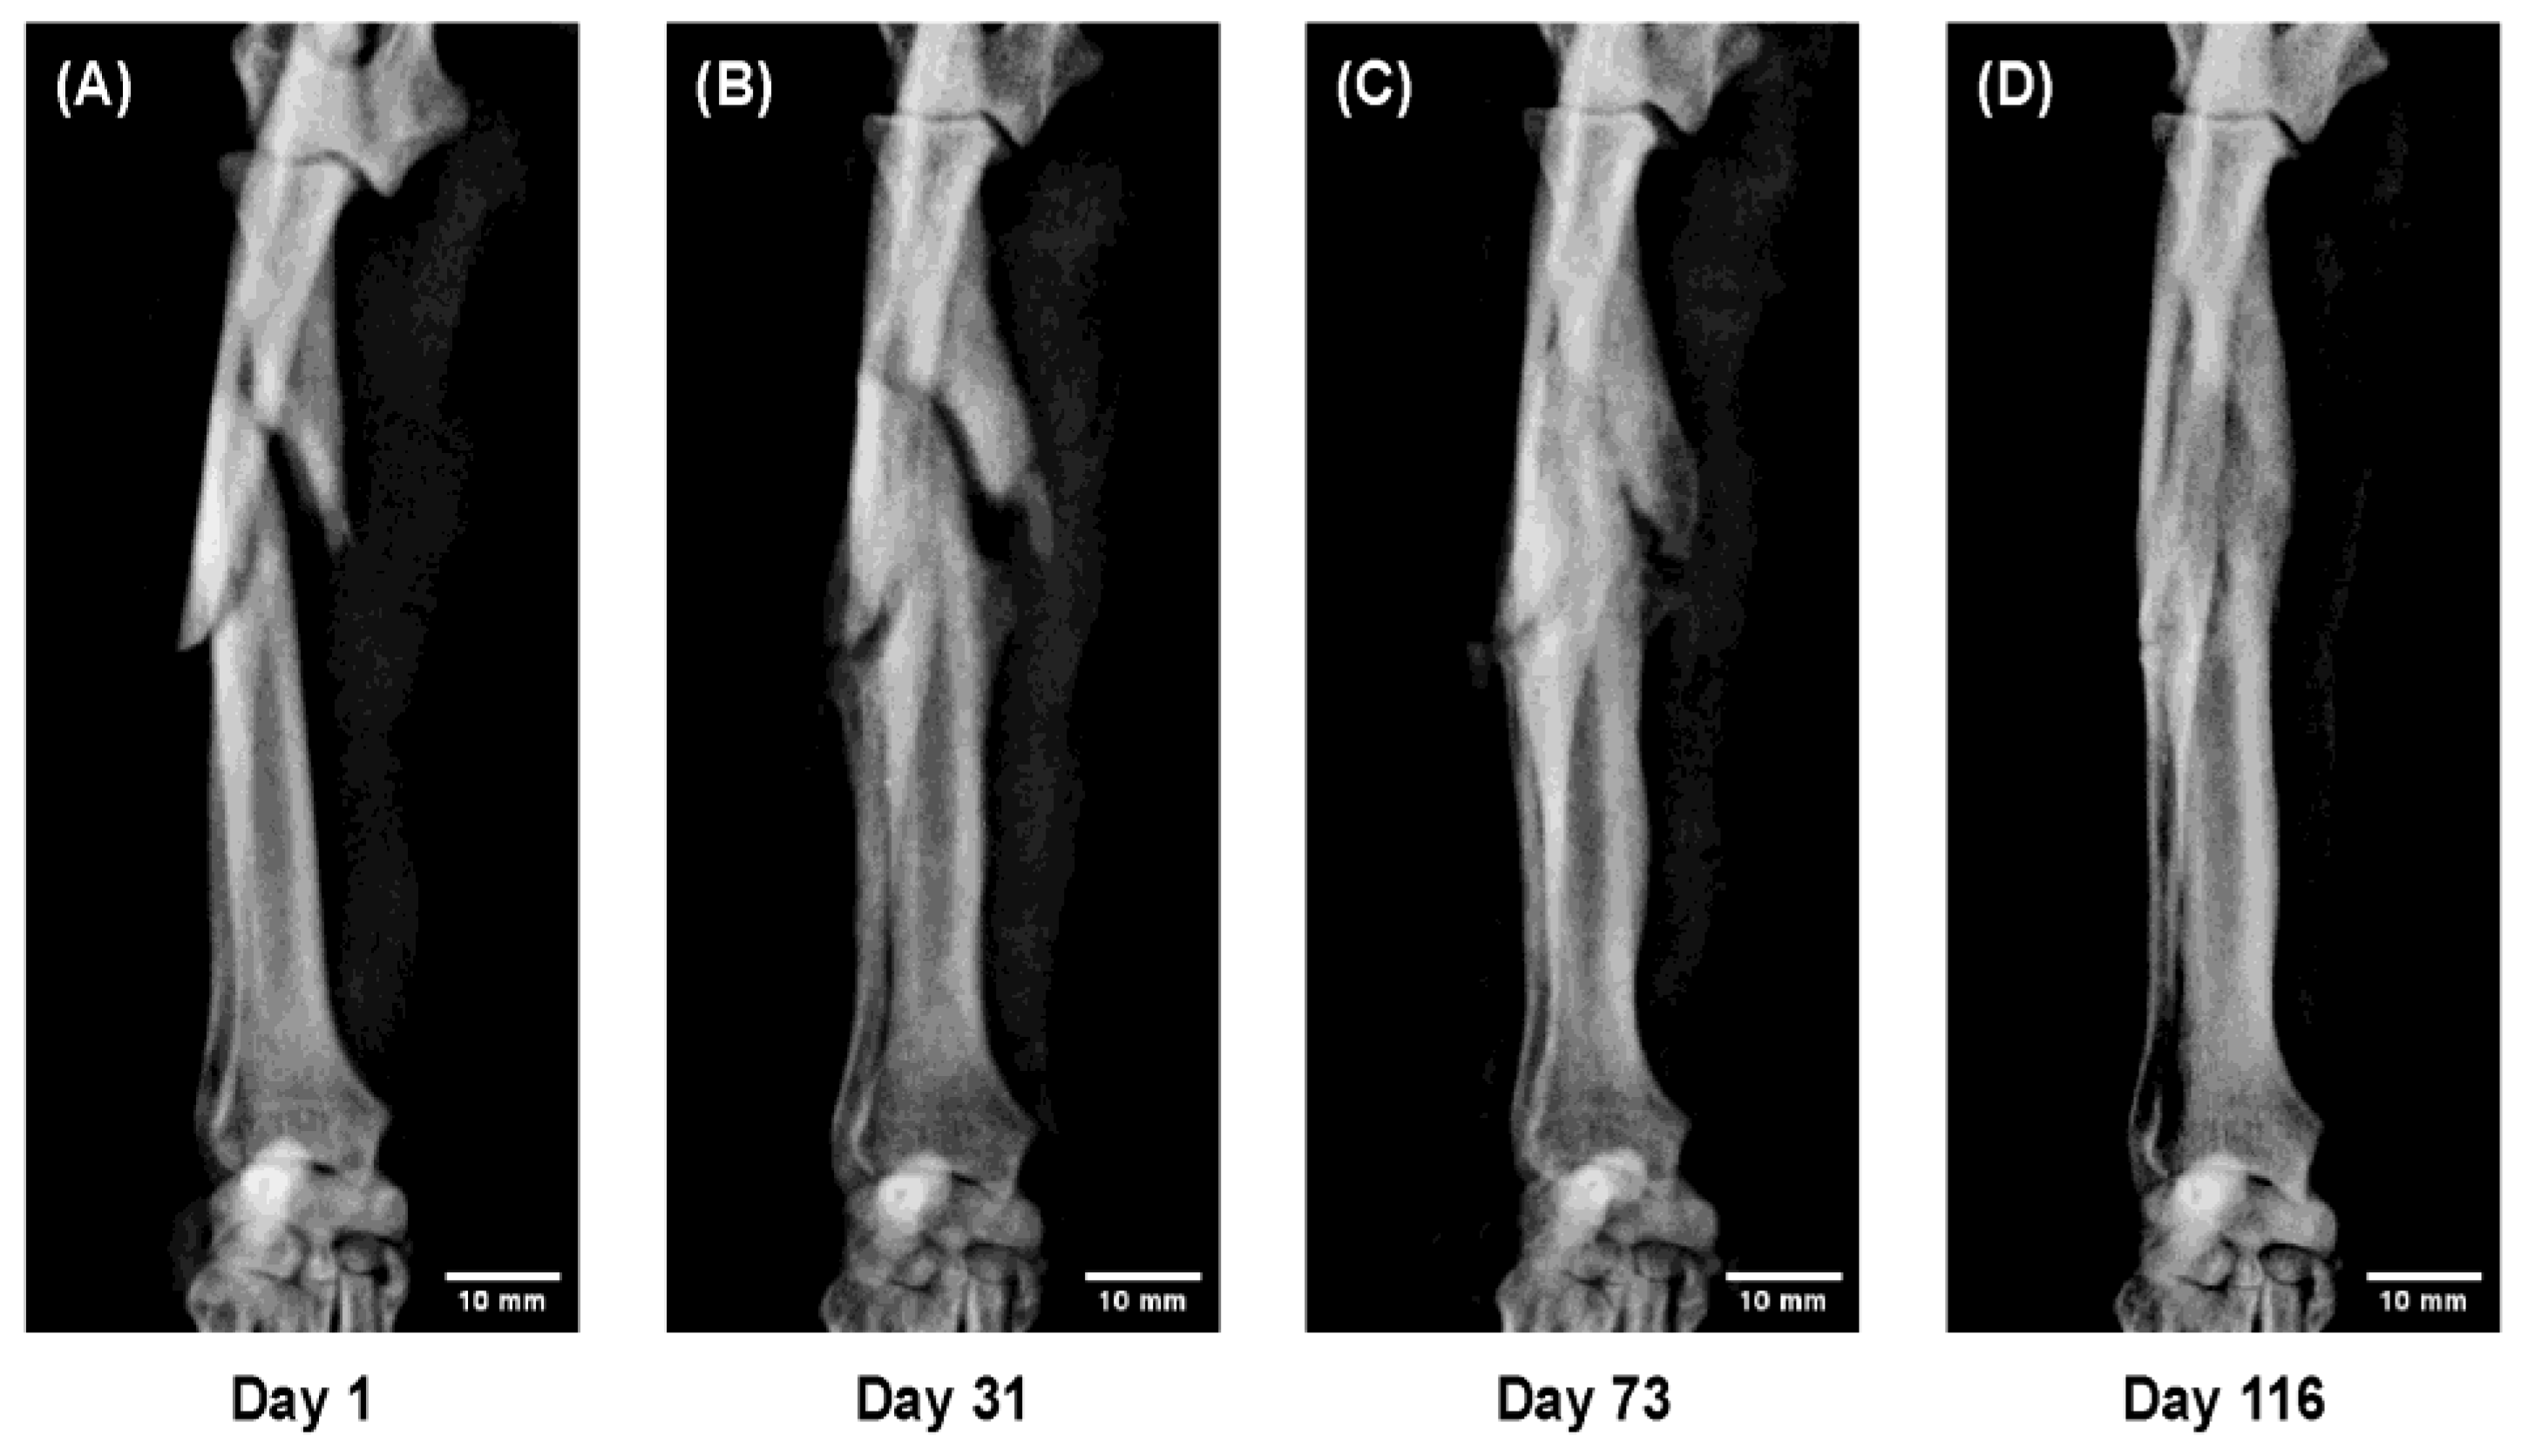

Figure 7.

Sequential radiographs showing a comminuted radial–ulnar fracture in a Toy Poodle, 9 years old, 6.7 kg. Despite severe displacement and fragmentation, successful bone union was obtained with 3D cast therapy, although callus formation was limited. (A) Day 1 after injury; temporary immobilization performed; 3D cast applied on Day 10. (B) Day 31: fragment thickening with maintained alignment. (C) Day 73: progressive callus formation and bony union. (D) Day 116: remodeling with restored bone morphology.

Figure 4. In a 13 month-old Pomeranian with extremely slender bones, both the radius and ulna achieved complete union despite the low body weight. Continuous radiographi cmonitoring under immobilization revealed the full course of indirect bone healing, including bridging callus formation across both bones, trabecular reconstruction, and re-establishment of the medullary cavity during remodeling.

Figure 7. In a 9 year-old Toy Poodle with a severely comminuted radial–ulnar fracture, complete bone union was achieved despite marked displacement and fragmentation. This case demonstrates that 3D cast therapy can be applied safely even in complex fractures and elderly cases, indicating its broad clinical applicability beyond simple or non-displaced fractures.